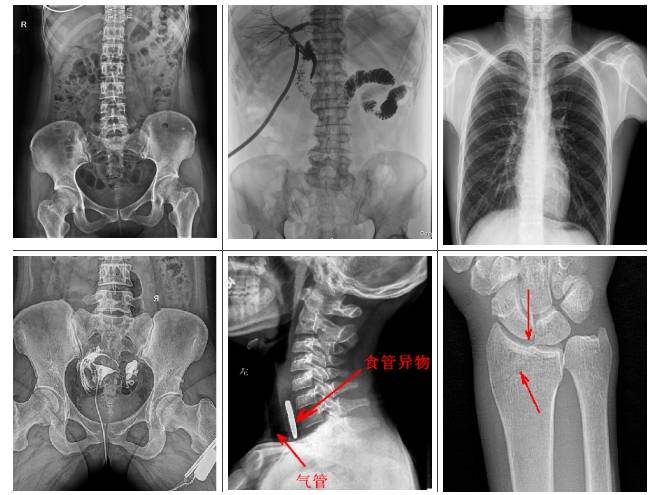

懸吊雙板DR是集拍片、造影于一體,可檢查多類疾?。?/p>

1.可檢查患者的呼吸系統(tǒng)疾病,比如是否有肺炎、肺腫瘤、肺結(jié)核、肺膿腫、胸腔積液以及氣胸等。

2.可檢查縱隔以及心臟系統(tǒng)的疾病、骨關(guān)節(jié)系統(tǒng)的疾病。

3.可做泌尿系統(tǒng)造影,子宮輸卵管造影、胃腸道造影,比如做鋇餐的檢查,觀察胃腸道是否有炎癥、腫瘤以及潰瘍等。

4.有職業(yè)病體檢篩查塵肺病功能,及發(fā)現(xiàn)區(qū)別肺部小結(jié)節(jié)功能。

普利德懸吊雙板DR采用動(dòng)靜態(tài)雙板配置,可實(shí)現(xiàn)毫秒級(jí)選板切換,專板專用,高效專業(yè)。可供各級(jí)醫(yī)院進(jìn)行人體頭部、頸部、胸部、腹部、腰椎、四肢等部位的臥位、正位、側(cè)位、斜位的數(shù)字化攝影、透視及造影檢查;適用于各級(jí)醫(yī)院臨床各個(gè)科室,滿足放射科、體檢中心、影像中心、內(nèi)科、外科

、急診科、骨科、創(chuàng)傷科、消化科等科室的多種臨床檢查需求。